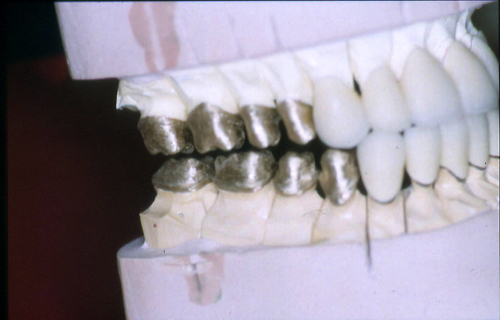

ABSTRACT El Bruxismo es una entidad patológica en la que concurren diferentes factores. Entre ellos el stress que conlleva consigo la vida moderna, constituye el Factor Predisponente sobre el que se ha abundado en innumerables tratamientos de tipo general, actuando sobre la psiquis y el comportamiento del individuo, ya sea con fármacos o bien mediante medios psicológicos. Sin embargo, como tantos desequilibrios provocados por el stress, confluyen siempre con un Factor Desencadenante, que en el caso del Bruxismo se encuentra en las desarmonías entre los componentes varios del Sistema Estomatognático. DESARROLLO Paciente varón, de 43 años, constitución atlética. A la inspección se observan desgastes oclusales que alcanzan la calidad de Facetas Parafuncionales, con dentina expuesta y empastes totalmente gastados y evidentes signos de falta de Disclusión Canina de ambos lados. Sobre dicho montaje se realiza un Encerado Progresivo de Diagnóstico, aportando en el mismo los elementos necesarios para obtener todos los principios básicos de una Oclusión Orgánica. FIG. 6 a 24 Una vez aprobado el fisiologismo de la oclusión en el articulador, se reproducen modelos de yeso con la nueva situación, y se estampa un SET UP en cada maxilar. FIG. 25/26 Procedemos entonces al tallado de las piezas correspondientes a la Guía Anterior, y rebasamos los estampados, creando en boca una nueva situación desoclusiva, que permanece en boca durante los pocos días que transcurren entre la primera y segunda visita de trabajo. FIG. 27/33 Ya abordando en esta segunda visita los sectores posteriores, tanto superiores como inferiores, tallamos siempre de manera supragingival, destacando la importancia vital de la forma obtenida en las provisionales, a las que abrimos plenamente las troneras para lograr una correcta higiene. FIG.34 a 43 FIG. 44 a 52 Efectuados los colados en oro y probados en boca, en el laboratorio se confecciona el bizcochado de la nueva Guía Anterior, la que puede o no copiarse de la Guía Anterior provisional, mediante la técnica denominada Trayectoria Funcionalmente Generada, que consiste en realizar en la platina del articulador un registro estereográfico sobre acrílico Duralay en polimerización. FIG. 57/58 Ajustados todos los detalles mediante esta técnica, se instala en boca en forma Provisional y se deja funcionando una semana o dos, al cabo de las cuales se chequean las disclusiones , los ajustes, la eficacia masticatoria, la carencia de sintomatología articular y muscular. FIG.59 a 63 PIE DE FOTO FIG.9 OBTENCIÓN DE LA GUÍA ANTERIOR FIG.10 Y 11 PITOMBOS. ALINEAC. TRIDIMENSIONAL FIG.12 PITOMBOS. DISCLUSIÓN DER. FIG.13 PITOMBOS. DISCLUSIÓN IZQ. FIG.14 WILSON INF. FIG.15 WILSON SUP. FIG.16 BOCA DE PEZ INF. FIG.17 BOCA DE PEZ SUP. FIG.18 VISTA OCLUSAL FIG.19 O.R.C. FIG.20 DISCLUSIÓN DERECHA FIG.21 CRESTAS TRIANG. INT. FIG.22 CRESTAS TRIANG. INT. FIG.23 CRESTAS TRIANG. INT. FIG 24 CRESTAS TRIANG. INT. FIG.59 DISCLUSIÓN IZQ. FIG.60 DISCLUSION IZQ. FIG.61 DISCLUSIÓN DER. FIG.62 DISCLUSION DER. FIG. 63 AJUSTE PERIFÉRICO

Se nos hace evidente la necesidad de proceder a rehabilitar todo el sistema, y se programa el correspondiente estudio oclusal, mediante un montaje en articulador semiajustable, el que se realiza luego de dos semanas de uso de una Férula de Desprogramación.